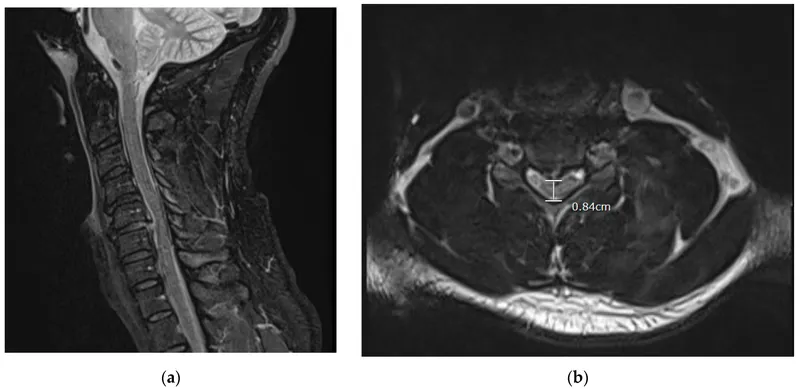

Acute Spinal Cord Compression:

- Causes: malignancy, trauma, epidural abscess/hematoma, disc herniation.

- Red Flags: severe back pain, progressive motor/sensory loss, sphincter dysfunction, saddle anesthesia.

- Management: STAT MRI. High-dose Dexamethasone (10mg IV bolus then 4-6mg Q6H). Urgent neurosurgical/oncological consult for decompression/radiotherapy.

⭐ In suspected acute spinal cord compression with neurological deficits, high-dose corticosteroids (e.g., Dexamethasone) should be administered immediately, even before definitive imaging, unless contraindicated.